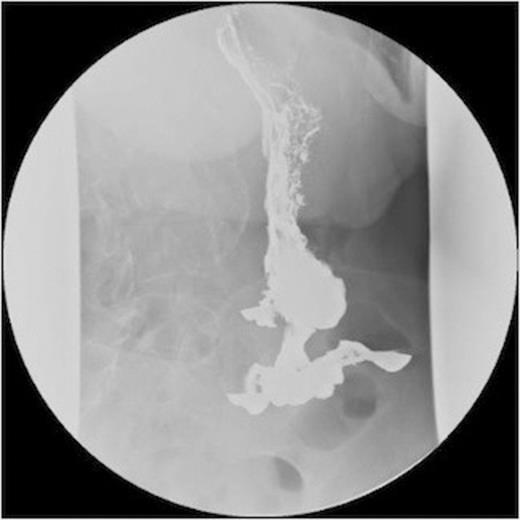

She then had a barium meal and follow through which clearly demonstrated a gastro-colic fistula. This was confirmed by colonoscopy which demonstrated the fistula. There were no signs of neoplasia and the no malignancy was witnessed on biopsy. These findings were confirmed on CT.

A series of radiographs from barium swallow demonstrating gastro-colic fistula